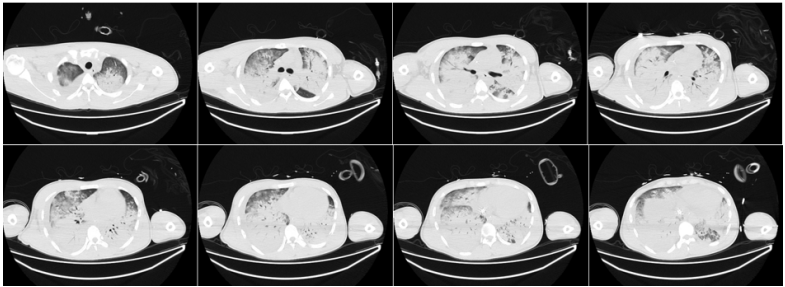

第3周第16天复查胸部CT:患者病变在逐渐吸收,病情较前好转(图5)。撤离ECMO,患者进入康复阶段。期间患者在气管镜下出现气道内右上叶出血。为了避免出血加重,整体调整了抗感染及抗凝治疗,并予西多福韦治疗。复查BALF腺病毒核酸仍为阳性,但患者整体状况、呼吸功能及肺部病变情况在逐渐改善

图片

图5  患者入院后胸部CT(第16天

第23天复查胸部CT:肺内仍有少量气压伤表现以及小结节(图6)第28天复查NGS发现,BALF中腺病毒序列数为22,血中腺病毒序列数为6。再予一次西多福韦。肾功能遗留少量损伤,仍在间断进行肾脏替代治疗治疗。第30天胸部CT可见病变较前明显吸收好转(图7)

图6  患者入院后胸部CT(第23天)

图7  患者入院后胸部CT(第30天)